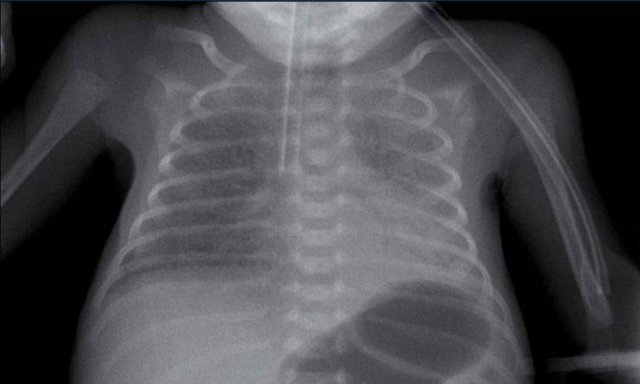

29 weeks + 1, day one. CPAP.

First look at the image.

What are the findings?

Findings:

• Reticulogranular opacification of lungs

• Air bronchogram

• Consolidation in the right lower lobe

• Heart, vessels and diaphragm are poorly defined.

• Malposition of umbilical vein catheter (arrow), probably in a pulmonary vein.

• Nasogastric tube (NG tube) in good position.

This is a severe case of RDS.

The differential diagnosis includes pulmonary infection due to the asymmetric consolidation.